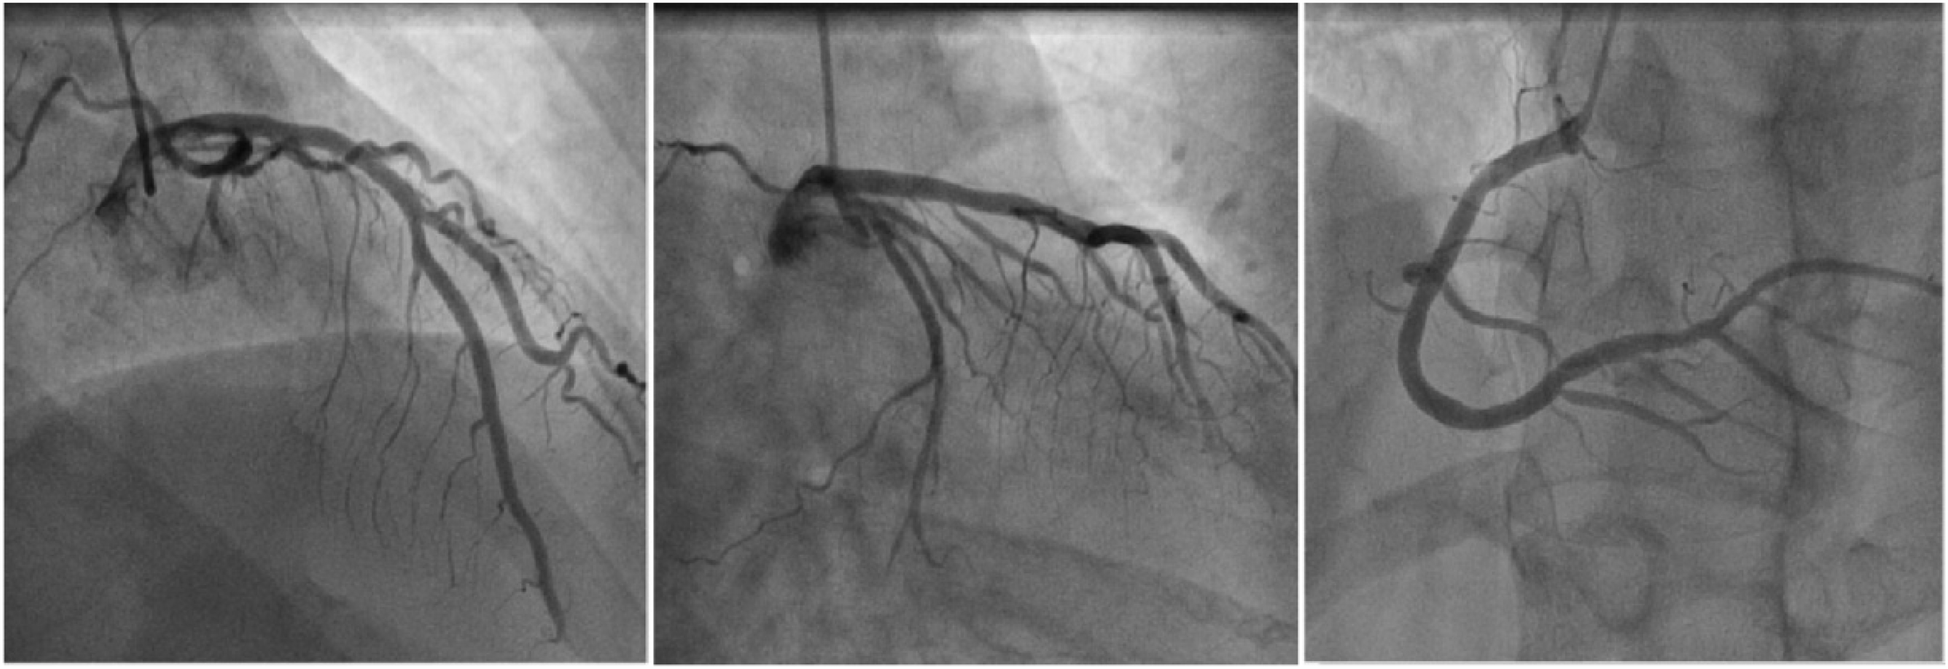

Physical examination on admission revealed a heart rate of 78 bpm and blood pressure of 127/71 mmHg. An electrocardiogram showed sinus rhythm, ST-T wave changes, and left bundle branch block, indicating myocardial ischemia. Echocardiography revealed aortic sclerosis, mild regurgitation of the mitral and tricuspid valves, normal cardiac structure, and a normal left ventricular ejection fraction. The patient had significant angina symptoms classified as Grade III according to the Canadian Cardiovascular Society Angina Grading Scale (CCS). Coronary angiography indicated mild coronary stenosis <50% (Figure 1). Myocardial perfusion imaging showed mild to moderate reversible myocardial ischemia in a portion of the left ventricular apex and part of the interventricular septum, involving approximately 12% of the left ventricular wall. Based on coronary angiography and imaging results, the patient exhibited slight enlargement of the left ventricular cavity during stress imaging compared to rest imaging, with a decrease in the left ventricular ejection fraction, suggesting a possible association with microcirculatory dysfunction (Figure 2).

Figure 1

Schematic diagram of coronary angiography. From left to right are the left anterior descending artery, circumflex artery, and right coronary artery.